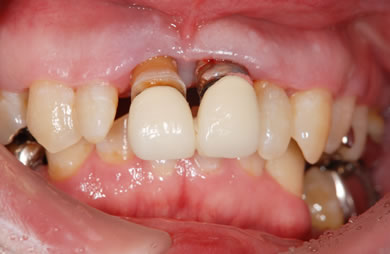

インプラントの症例写真 IMPLANT

骨再生スピードインプラント治療+セラミック治療

| 主訴 | 上の前歯が6ヶ月程前からぐらつき出した。 | ||||||||||||||||||||||||||||||||

| 治療方針 | 審美的・機能的回復をなるべく早くはかる為、抜歯と同時にインプラント治療を行う。また、奥歯に関しては歯周病が進行しているものの、歯の保存が可能な状態である為、エムドゲインを使用し、組織再生をはかる。 | ||||||||||||||||||||||||||||||||

| 治療内容 | インプラント3本(抜歯即日スピードインプラント+GBR)、ハイブリッドセラミック4本、オールセラミックラミネートベニア2本、エムゲドイン組織再生療法 | ||||||||||||||||||||||||||||||||